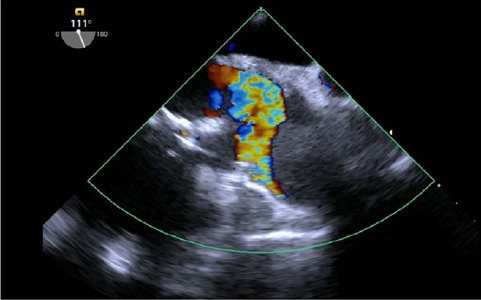

A 58-year-old man, who has undergone ascending aorta replacement, started to complain of pain in the lower limbs, shortness of breath, and progressive fatigue a few months after surgery. Transthoracic and transesophageal Doppler echocardiographies revealed a diseased bicuspid aortic valve and a subocclusive mass in the ascending aorta. Thoracic computed tomography angiography confirmed the presence of a subocclusive mass, pseudoaneurysm formation, and a distorted shape of the Dacron® graft. The patient underwent urgent surgery to remove the mass, which appeared to be a thrombus, and aortic valve and ascending aorta replacement. Kinking of vascular graft has been reported including surgical techniques to correct the excessive length to avoid gradients and guarantee laminar flow. When kinking is severe, high gradients and hemolysis can be detected. However, thrombus formation in the ascending aorta segment is less likely, due to the high blood velocity flow. Therefore, several concurrent causes should be considered. In this case, the most probable explanation for thrombus formation was kinking of a too long Dacron® graft, combined with extrinsic compression effect of the graft by the pseudoaneurysm at the anastomosis site and anomalous flow directed from the diseased bicuspid aortic valve. Various grades of Dacron® graft kinking might occur following ascending aorta replacement and undiagnosed at follow-up especially if resulting in mild symptoms, thus, careful visual and echocardiography evaluation should be done at the end of surgery. Finally, distorted Dacron® graft might trigger thrombus formation when inflammation and coagulation processes are set off during bacteria or viral infection.

Abstract Image